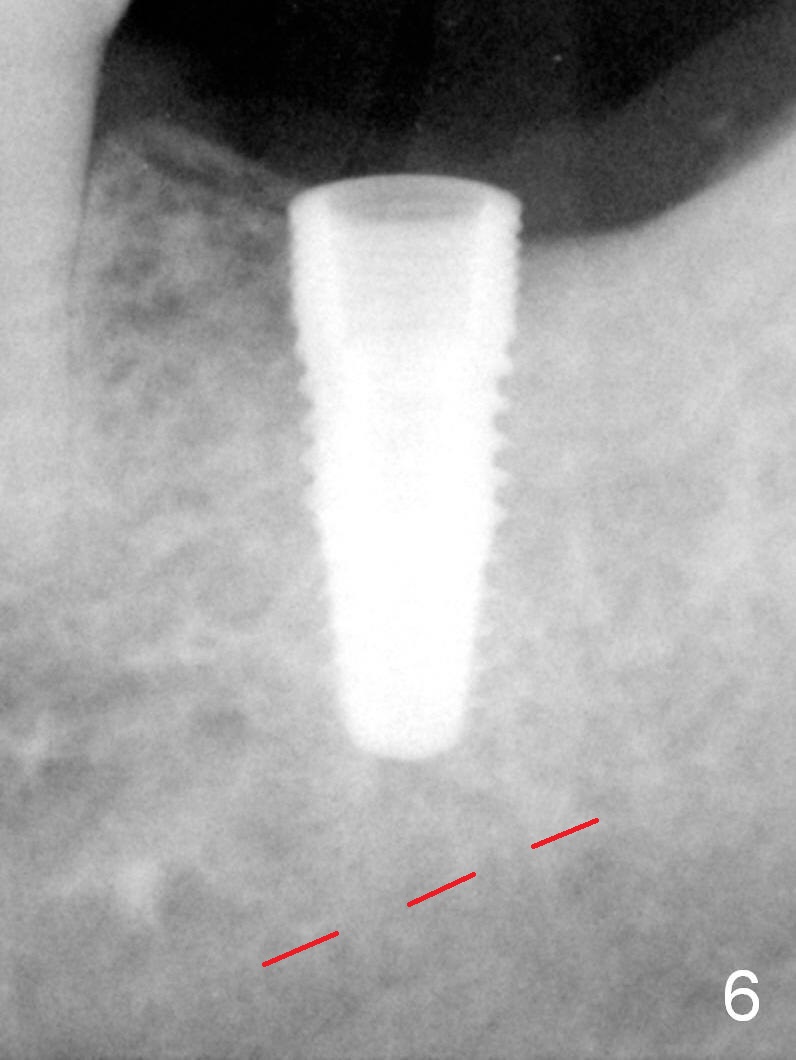

A 48-year-old lady is a dental phobic, requesting extraction of the lower left 2nd molar (Fig.1). She returns for implant placement 9 months post extraction (Fig.2). The ridge is mildly to moderately atrophic. It appears that a 5x12 mm implant is appropriate for the site (Fig.3). For safety, osteotomy is initiated at the depth of 10 mm; it appears that there is enough height for a 12 mm implant (Fig.4). The depth is controlled by drill stopper (Fig.5 S). Finally a 5x12 mm implant is apparently safely placed (Fig.6). A healing abutment is placed and the incision is sutured with 4-0 Chromic gut (Fig.7). Perio dressing is applied around the healing abutment for wound protection (Fig.8). It appears that the healing abutment (Fig.8': *) helps stabilize the perio dressing, which remains in place 1 week postop. When the perio dressing is removed, the wound around the healing abutment is healing (Fig.9). There is no bone loss around the implant 3 months postop (Fig.10 (H: healing abutment), or 16 months postop (i.e., 9 months post cementation, Fig.11,12). The patient complains of pain when she chews with the implant crown, but pain stops whenever she does not bite. Percussion does not elicit any discomfort. The gingiva is healthy. There is possibility of the buccal plate being thin or the lingual plate being perforated in the submandibular fossa. If the discomfort remains the same next 6 months, CBCT will be prescribed.